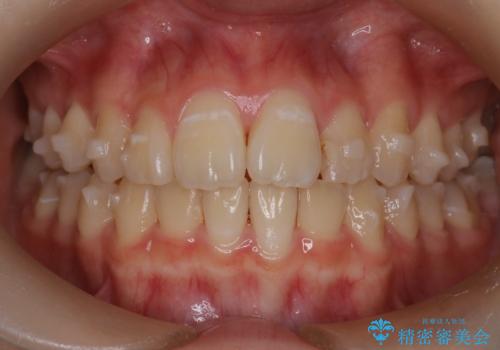

マウスピース矯正で前歯のガタツキを改善! 短期間で治療完了

- 前歯のガタツキが気になるとのことで来院されました。

前歯のガタツキに加え、奥歯の噛み合わせにも問題があったため、マウスピース矯正で治療し改善しました。